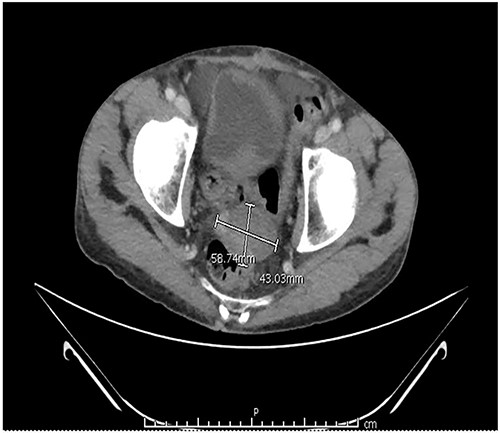

Two months after the tumor was grossly resected and 1 month into Imatinib treatment, the patient presented to the Emergency Department with complaint of abdominal discomfort, constipation and nausea. CT abdomen and pelvis noted mid small bowel distention, suggestive of partial small bowel obstruction with mild ascites. Importantly, a mass-like focus measuring 5 × 3.8 cm was found in the pelvis anterior to the rectosigmoid junction (Fig. 3). A nasogastric tube was subsequently placed and the patient was administered empiric antibiotics. Considered a failure of conservative management, the patient was taken to the operating room again for an exploratory laparotomy, lysis of adhesions and debulking of the mass. The patient tolerated the procedure well with no complications. The patient maintained a typical postoperative course and was discharged with oncological follow-up and continued Imatinib treatment. On 2 and 4 months follow-up CT, the pelvic mass measured 4.1 × 3.3 and 2.6 × 2.7 cm (Fig. 4), respectively.

CT abdomen and pelvis with contrast identified small bowel distention and a mass-like focus measuring 5 × 3.8 cm in the pelvic region.